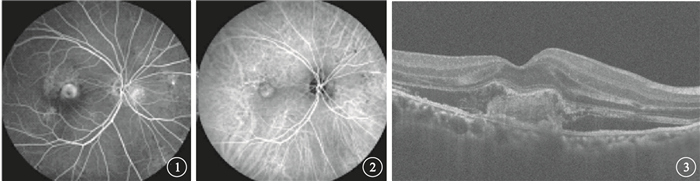

前瞻性、無對照、開放性研究。2014年4~8月在武漢大學人民醫院眼科經熒光素眼底血管造影(FFA)和吲哚青綠血管造影(ICGA)檢查確診為滲出型AMD的20例患者20只眼納入本研究。其中,男性19例19只眼,女性1例1只眼。年齡52~79歲,平均年齡(66.65±8.94)歲。所有患眼均行最佳矯正視力(BCVA)、眼壓、眼底彩色照相、FFA、ICGA和光相干斷層掃描(OCT)檢查。BCVA檢查采用糖尿病視網膜病變早期治療研究視力表進行;眼壓測量采用日本Topcon公司非接觸眼壓計進行;眼底彩色照相采用日本KOWA nonmydα-D免散瞳眼底照相機進行;FFA檢查采用德國海德堡共焦激光眼底造影儀進行;OCT檢查采用蔡司Cirrus HD-OCT進行,由同一位醫師采用512×128模式及高清掃描模式測量中心視網膜厚度(CRT),存在偏差者行人為校準。患眼BCVA為8~80個字母,平均BCVA為(41.20±22.61)個字母。FFA、ICGA檢查發現,所有患眼黃斑區CNV病灶滲漏明顯(圖 1,2)。OCT檢查發現,所有患眼黃斑區視網膜水腫,伴神經上皮脫離(圖 3)8只眼,伴視網膜色素上皮(RPE)脫離3只眼;CRT為152~770μm,平均CRT為(345.25±131.96)μm。所有患眼均符合滲出型AMD的臨床診斷標準[8-11]。

前瞻性、無對照、開放性研究。2014年4~8月在武漢大學人民醫院眼科經熒光素眼底血管造影(FFA)和吲哚青綠血管造影(ICGA)檢查確診為滲出型AMD的20例患者20只眼納入本研究。其中,男性19例19只眼,女性1例1只眼。年齡52~79歲,平均年齡(66.65±8.94)歲。所有患眼均行最佳矯正視力(BCVA)、眼壓、眼底彩色照相、FFA、ICGA和光相干斷層掃描(OCT)檢查。BCVA檢查采用糖尿病視網膜病變早期治療研究視力表進行;眼壓測量采用日本Topcon公司非接觸眼壓計進行;眼底彩色照相采用日本KOWA nonmydα-D免散瞳眼底照相機進行;FFA檢查采用德國海德堡共焦激光眼底造影儀進行;OCT檢查采用蔡司Cirrus HD-OCT進行,由同一位醫師采用512×128模式及高清掃描模式測量中心視網膜厚度(CRT),存在偏差者行人為校準。患眼BCVA為8~80個字母,平均BCVA為(41.20±22.61)個字母。FFA、ICGA檢查發現,所有患眼黃斑區CNV病灶滲漏明顯(圖 1,2)。OCT檢查發現,所有患眼黃斑區視網膜水腫,伴神經上皮脫離(圖 3)8只眼,伴視網膜色素上皮(RPE)脫離3只眼;CRT為152~770μm,平均CRT為(345.25±131.96)μm。所有患眼均符合滲出型AMD的臨床診斷標準[8-11]。